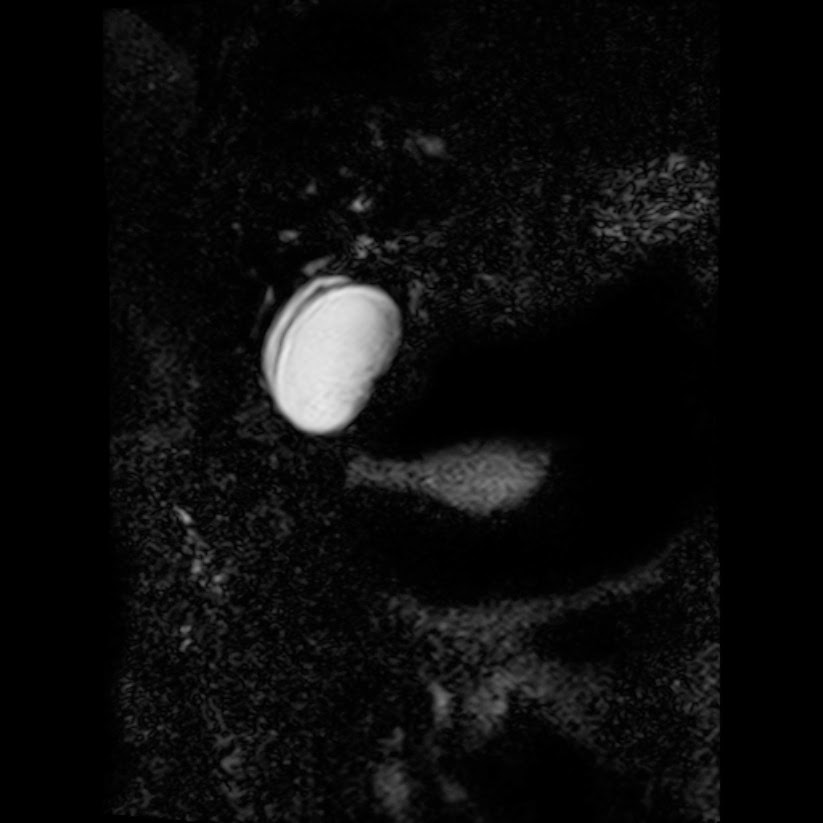

Caso interesante #5

Paciente con dolor en hipocondrio derecho.